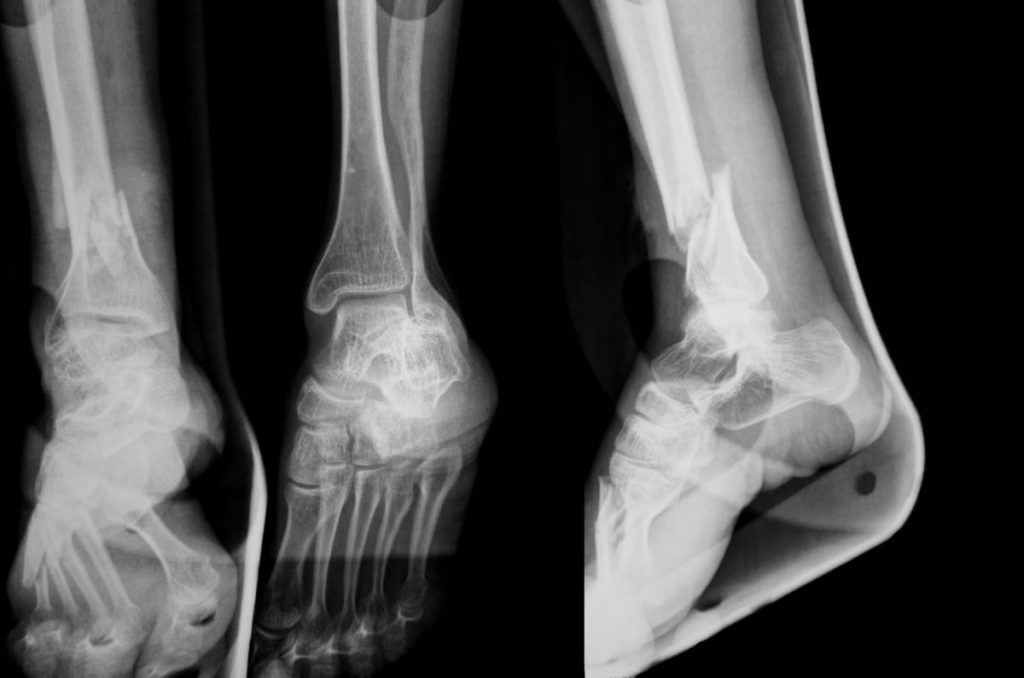

Medical Imaging in Differentiating the Diabetic Charcot Foot from Foot Health Facts Charcot Prompt diagnosis and treatment are. Diabetes is the main cause of charcot foot. Web charcot foot weakens bones in the foot and is common among people with diabetes. Diabetes can lead to peripheral neuropathy, which is necessary for charcot. Advanced charcot foot change your foot's shape if your bones and joints collapse or break. Web charcot foot, also called charcot. Foot Health Facts Charcot.